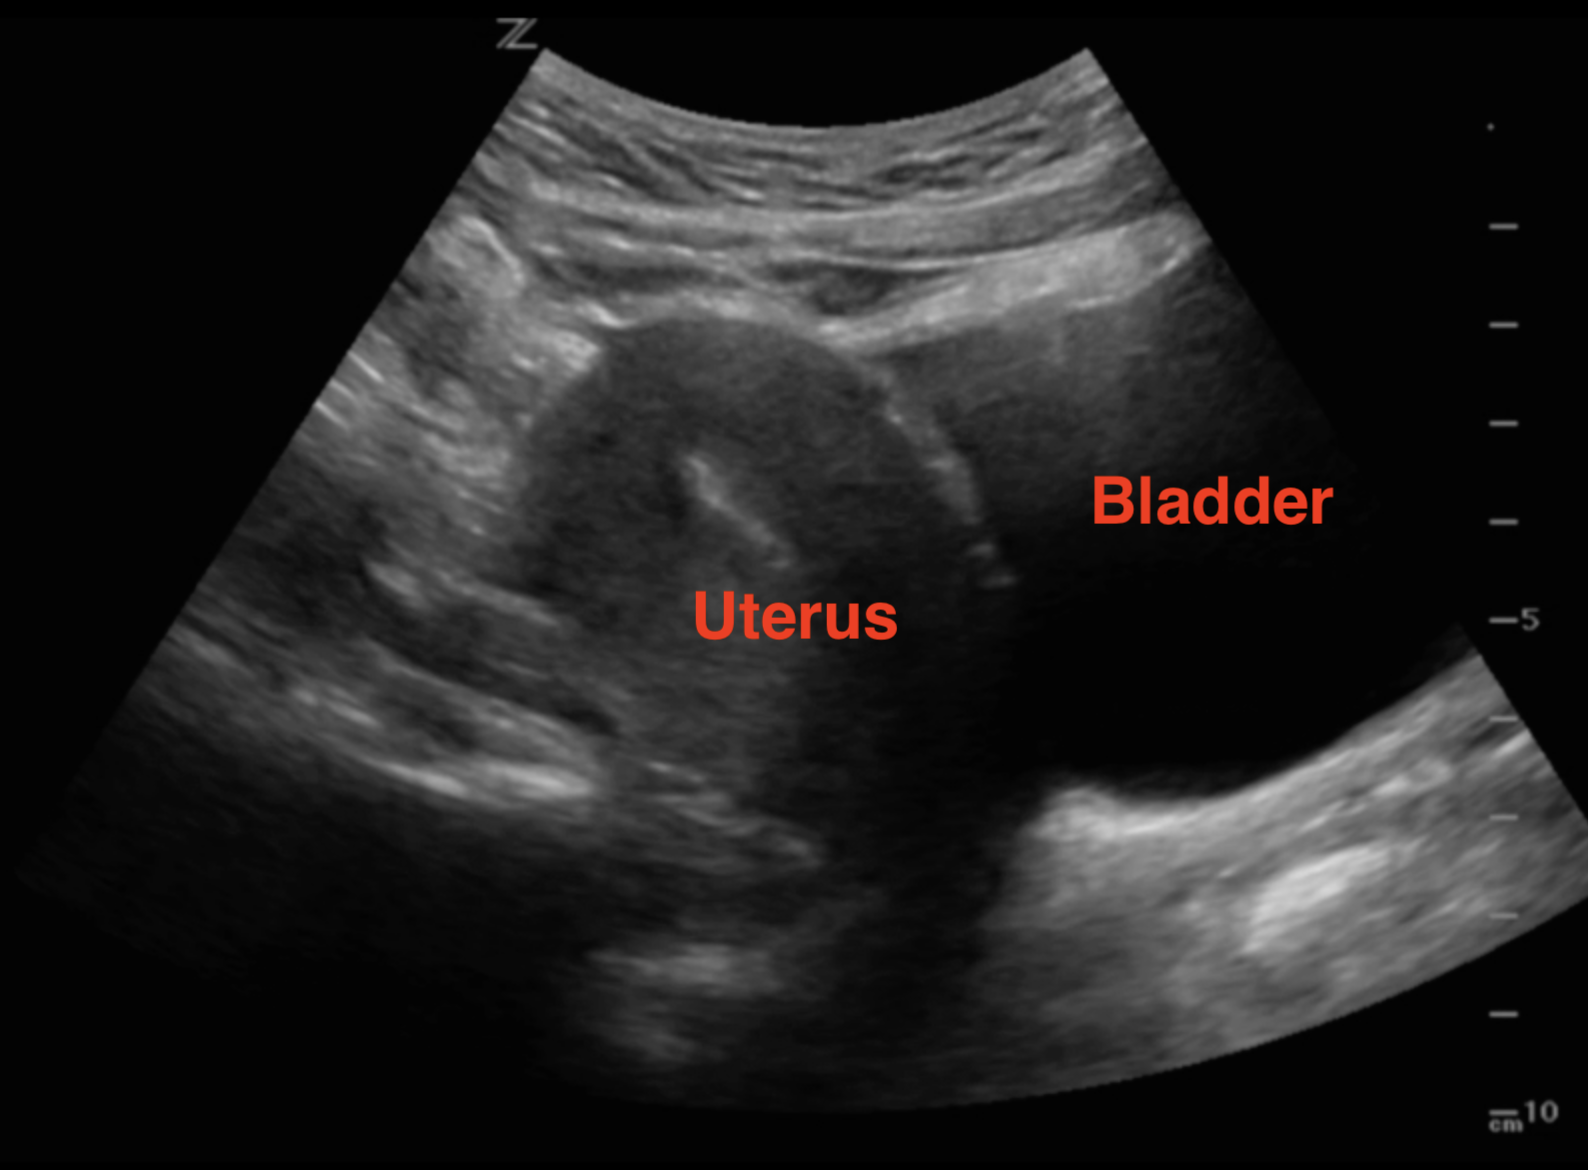

- Rotate the probe towards the patient’s head to and fan left to right in the sagittal plane (Illustrations 5 & 6, Video 2)

- Illustration 5. Illustration of sagittal approach and relevant anatomy. Probe indicator toward patient’s head (star)

- Illustration 6. Pelvis sagittal view with relevant anatomy

- Video 2. Sagittal view with bladder anterior inferior and uterus superior